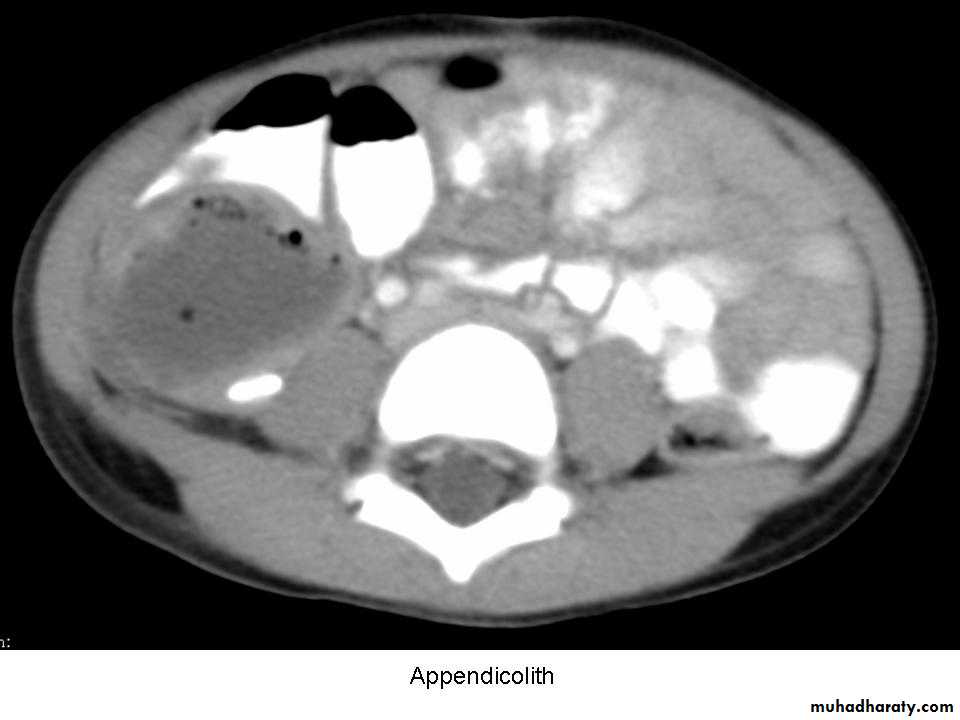

3- Obstruction of the appendix lumen

- Lymphoid hyperplasia

- faecolith (composed of inspissated faecal material,

calcium phosphates, bacteria and epithelial debris

- faecolith obstruction of the appendix lumen